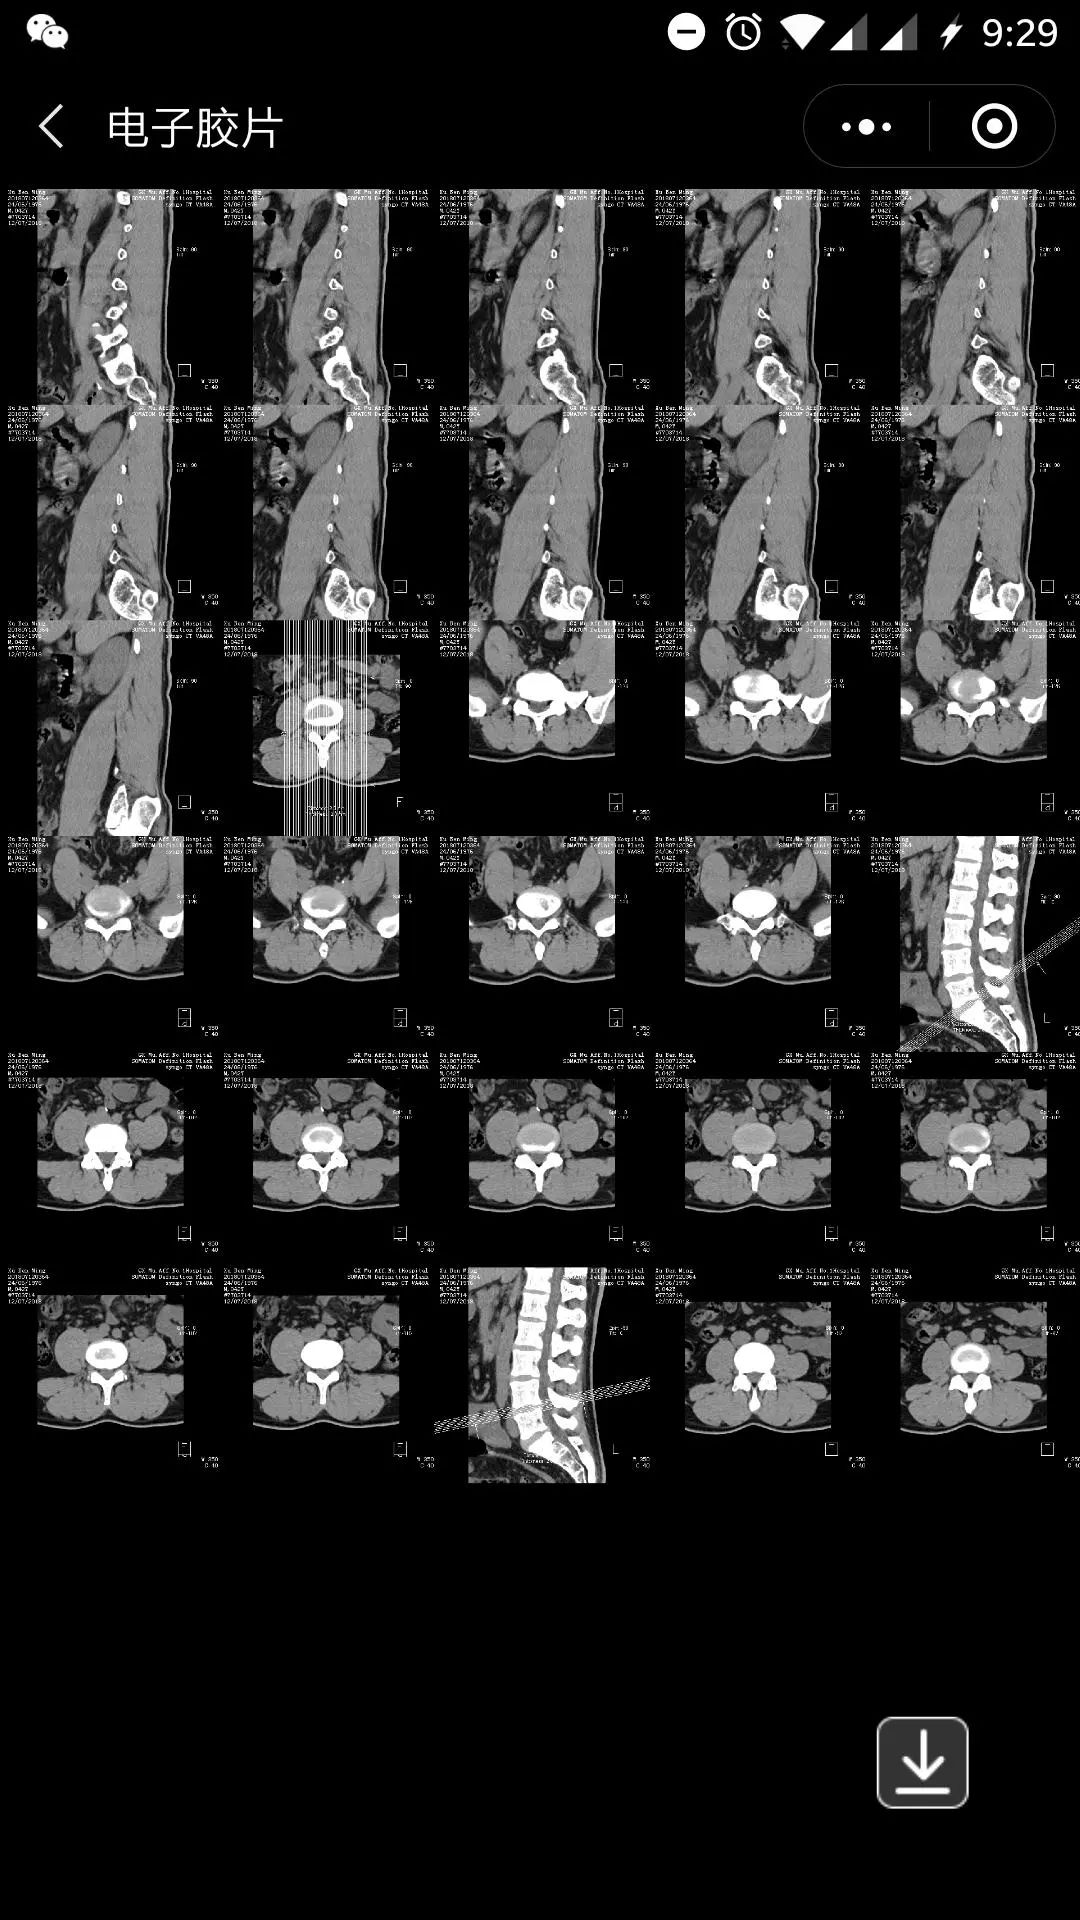

2019年起,在广西医科大学第一附属医院放射科做DR、CT、MR等检查后,不用再取一袋袋又大又重的胶片了。医生和患者只需在手机、电脑等信息联通终端上操作就能随时调阅查看检查胶片。

我院放射科主任龙莉玲教授介绍,“云胶片”是存储和共享的数字化胶片,可实现胶片即存即取、即用即看、智能终端调阅等功能,达到无线联接患者、医生和医院的作用。

电子影像卡里的图像有两种形式,一种是云胶片形式,一种是原始数据形式,都可以浏览,云胶片形式可以下载一次,以相片的形式在任何显示器打开,可以放大等操作,卡里的资料可以无数次浏览,保存15~20年(医疗资料保存规定年限)。